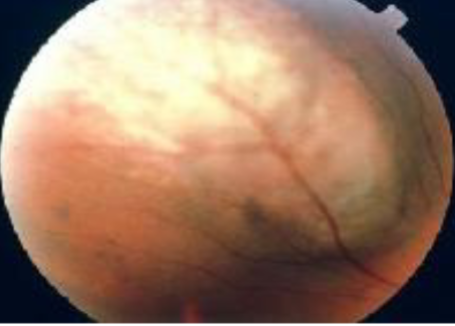

exophytic

retinoblastoma type

yellowish subretinal mass lesion often underlying a serous RD

total RD risk

tumor is difficult to view

retinoblastoma

retinoblastoma

retinoblastoma